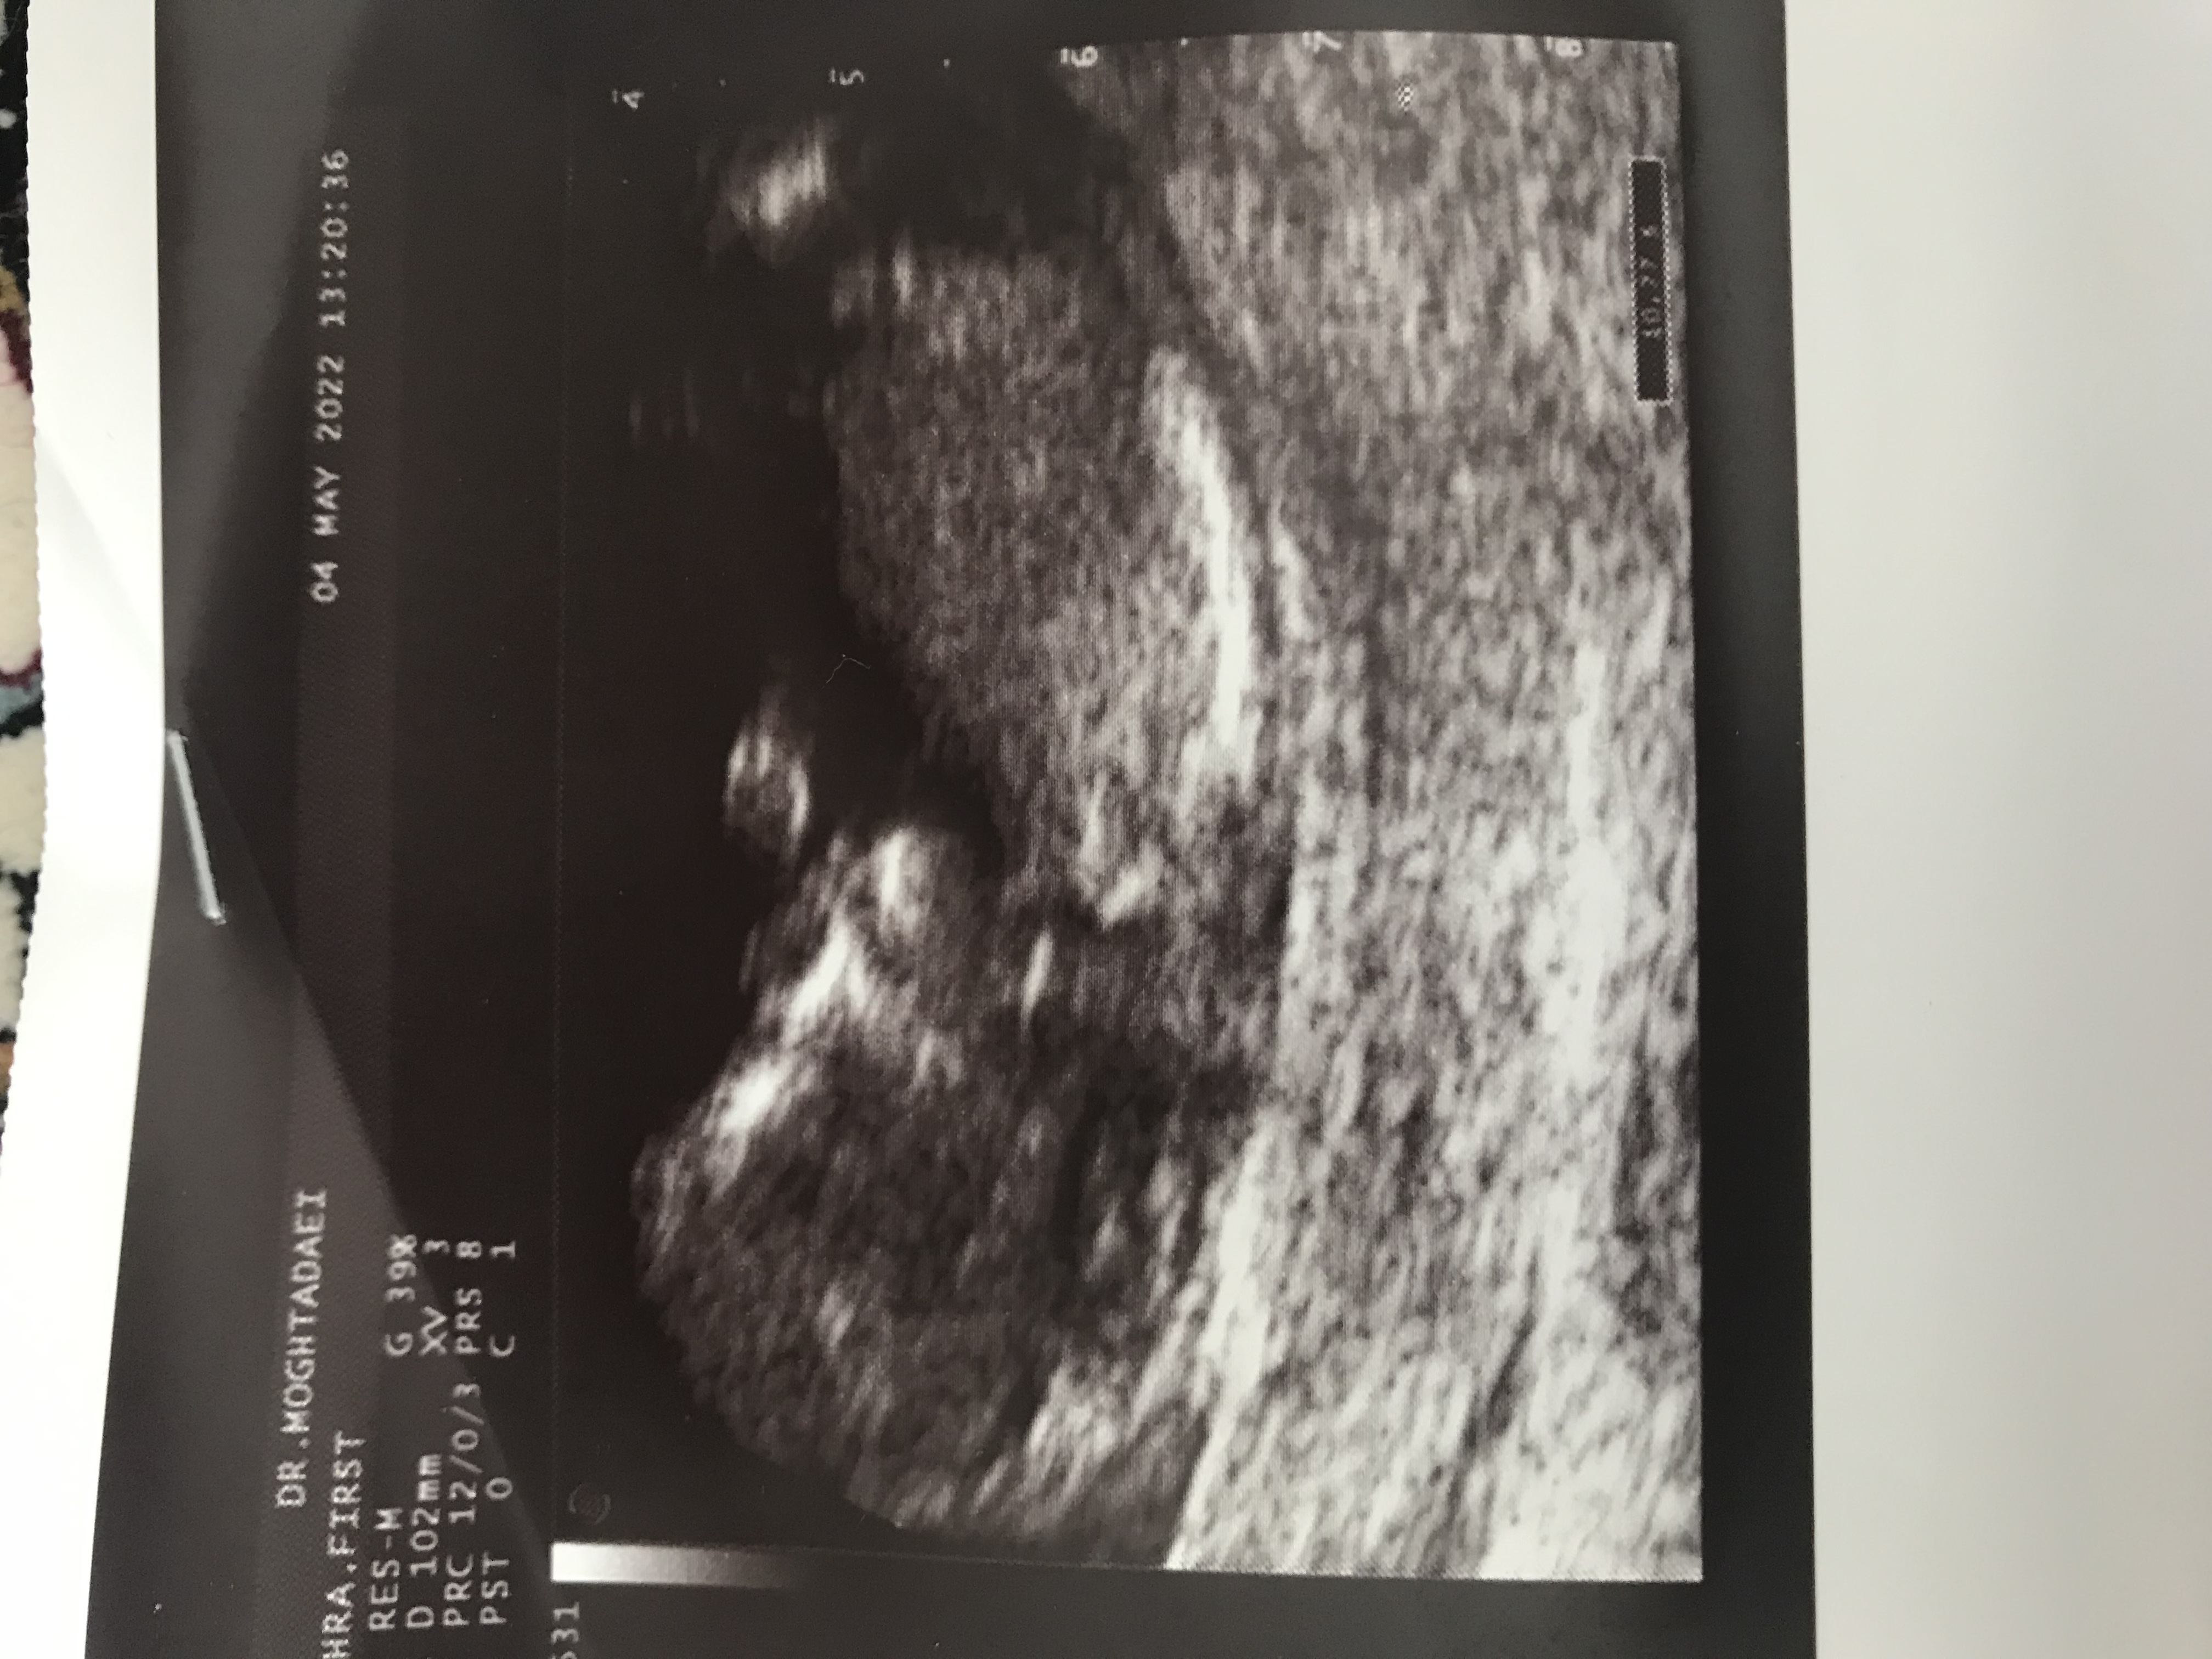

zahrabm عضویت: 1397/02/16 تعداد پست: 7943 ای خدا قلبم رفت....ببین تو ان تی گفت دختره؟ میشه عکس ان تیو بزاری من دلم میره واسه دخملی نه من بخاطر بارداری قبلیم مجبور شدم سلفری بدم تو اون مشخص شد دخترهاینم گوووووجه گیلاسی من😍😍😍😍 درانتظار نی نی😍بیبیچکم روز میلاد امامسجاد ۱۷ اسفند ۱۴۰۰ مثبت شد❤️ دختر قشنگم ۱۰ مهر ۱۴۰۱ تو۳۴هفته بدنیا اومد و شد تموم دنیامون🥰

شایلین1401 مدیر استارتر عضویت: 1401/02/18 تعداد پست: 8604 نه من بخاطر بارداری قبلیم مجبور شدم سلفری بدم تو اون مشخص شد دختره اینم گوووووجه گیلاسی ... وای خدا قربونش ببین شبیه واسه منم بنظرت؟

zahrabm عضویت: 1397/02/16 تعداد پست: 7943 وای خدا قربونش ببین شبیه واسه منم بنظرت؟ همشون شبیه همن😅😍برا تو فندوق تره🥰 درانتظار نی نی😍بیبیچکم روز میلاد امامسجاد ۱۷ اسفند ۱۴۰۰ مثبت شد❤️ دختر قشنگم ۱۰ مهر ۱۴۰۱ تو۳۴هفته بدنیا اومد و شد تموم دنیامون🥰

شایلین1401 مدیر استارتر عضویت: 1401/02/18 تعداد پست: 8604 همشون شبیه همن😅😍 برا تو فندوق تره🥰 بنظرت واسه منم دختره؟